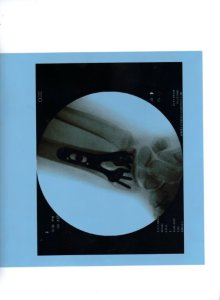

Go ahead and laugh. I did and so did she. She even laughed when she found it was broken in two places and required surgery. She laughed during pre-op and laughed post-op. She laughed when she viewed the x-ray showing her dandy new titanium plate and pins.